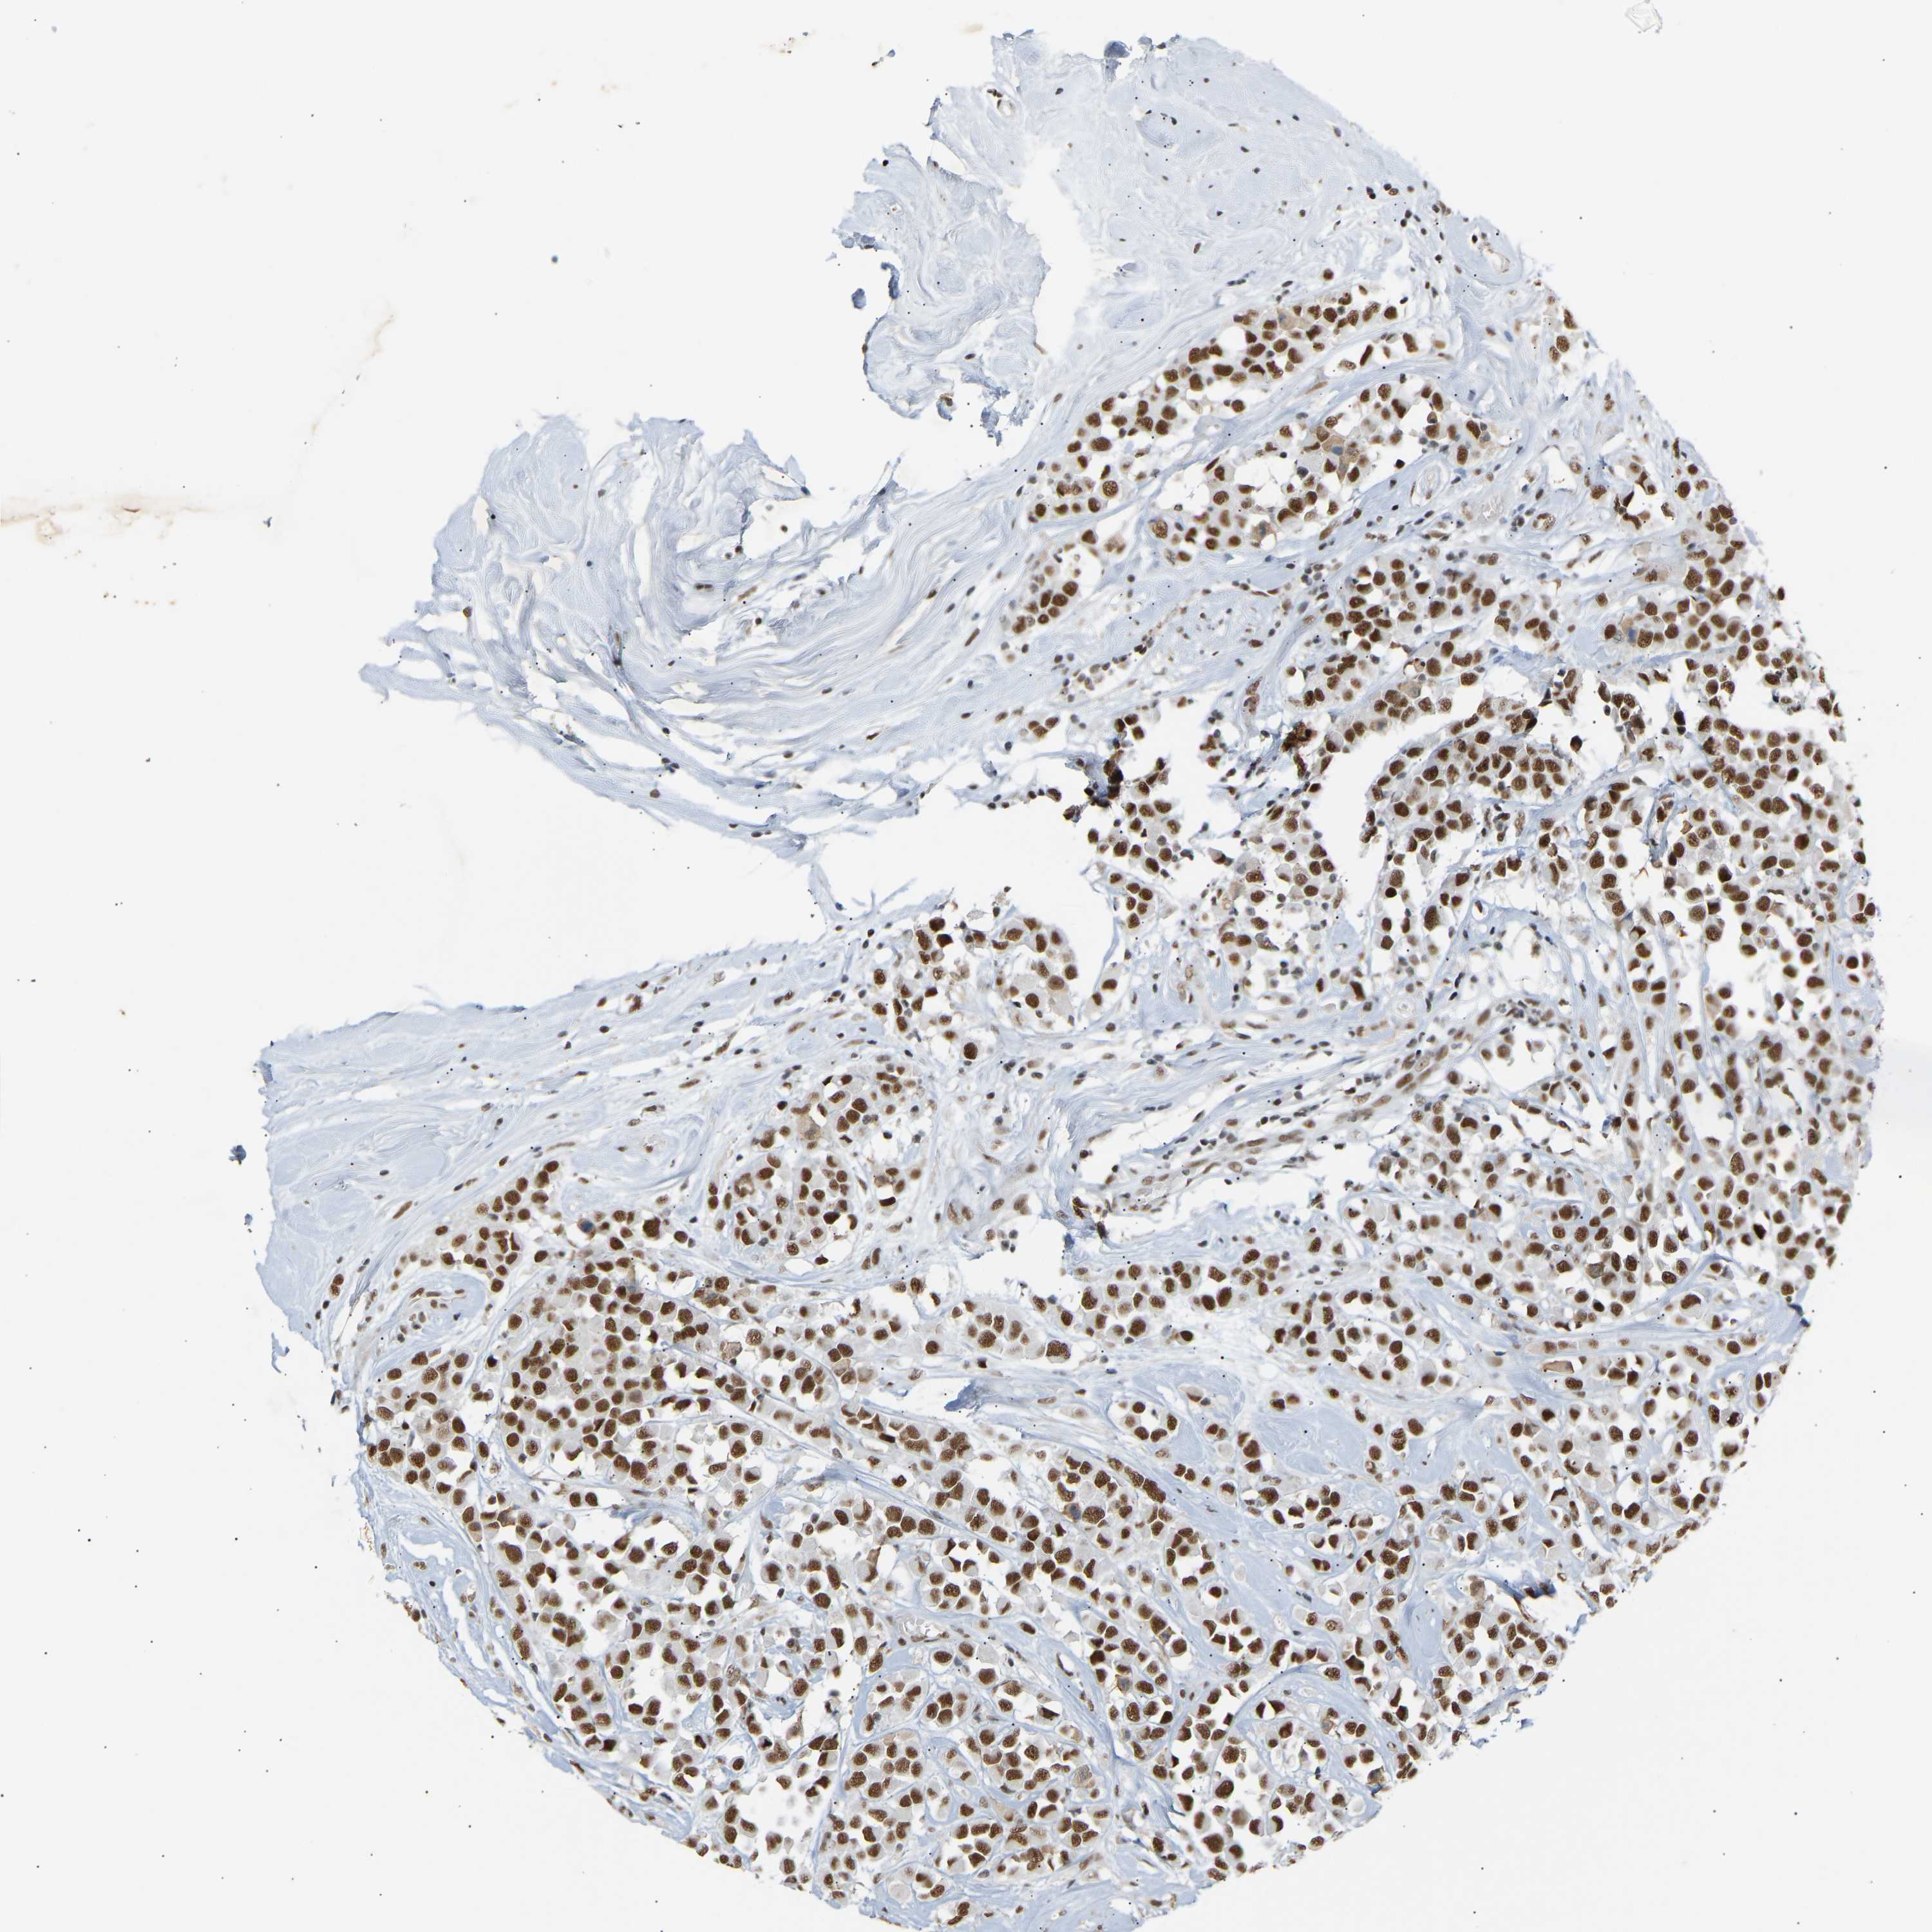

CANCER BREAST CANCER Show tissue menu

BRCA TCGA BRCA VALIDATION PROTEIN EXPRESSION